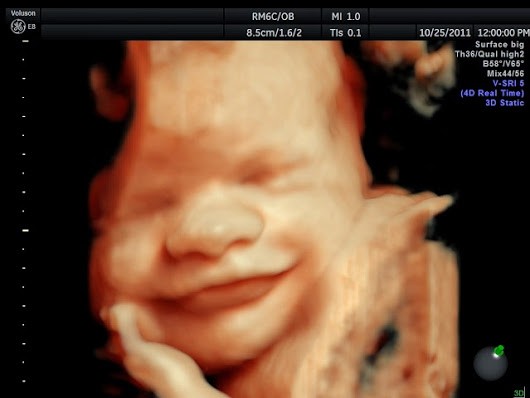

También, gracias a los avances tecnológicos, cada vez es más fácil observar con más detalle al feto. En muchos exámenes ginecológicos ya pueden apreciarse otra clase de movimientos, algunos bastante curiosos.

Ríe y llora

El llanto puede percibirse en las ecografías, ya que el labio inferior del bebé tiembla. También puede reír, ya que a partir de la semana 28 de embarazo el niño ya empieza a gesticular. Ambas expresiones, junto con el bostezo, serán las más habituales que se perciban en él una vez nazca.